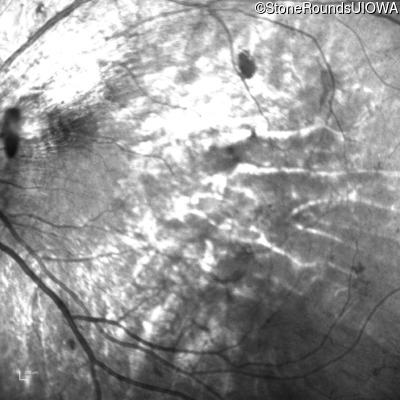

Infrared Fundus Photograph - Left - 5/160

Exemplar